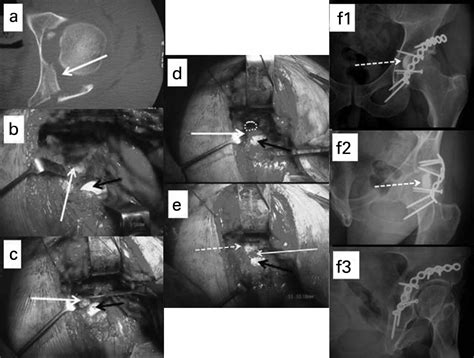

The treatment of an impaction of fracture depends on the location, severity, and associated injuries. The primary goals of treatment are to stabilize the fracture, restore alignment, and promote healing. Treatment options include:

• Surgical Management: More severe impaction fractures often require surgical intervention. Surgical options include:

Open Reduction and Internal Fixation (ORIF): This procedure involves surgically realigning the bone fragments and securing them with plates, screws, or rods. ORIF is commonly used for fractures in the long bones, pelvis, and spine.

Case Study 1: Femur Fracture

A 35-year-old male was involved in a high-speed motor vehicle accident. He sustained a severe femur fracture with impaction of the bone fragments into the soft tissue. The patient underwent surgical intervention with open reduction and internal fixation. Post-operative rehabilitation included pain management, range of motion exercises, and strengthening exercises. The patient made a full recovery and returned to his pre-injury level of function within six months.